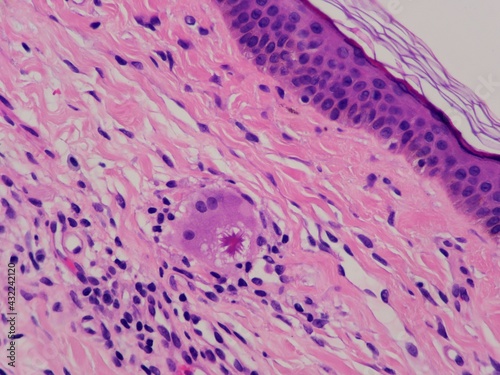

Mikrofotografi - Plakater, Poster, Billeder på lærred